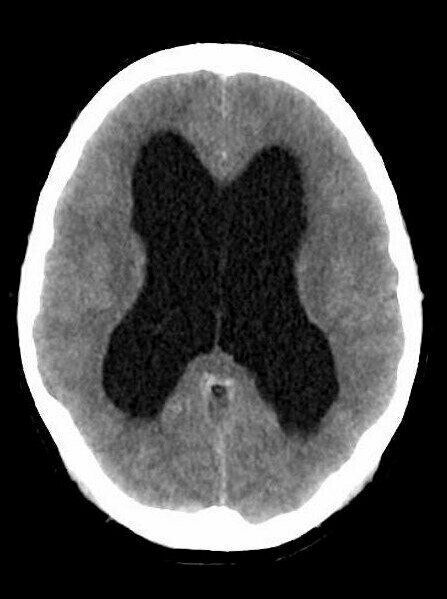

Non-communicating hydrocephalus, with dilated lateral and third ventricle, but normal fourth ventricle.